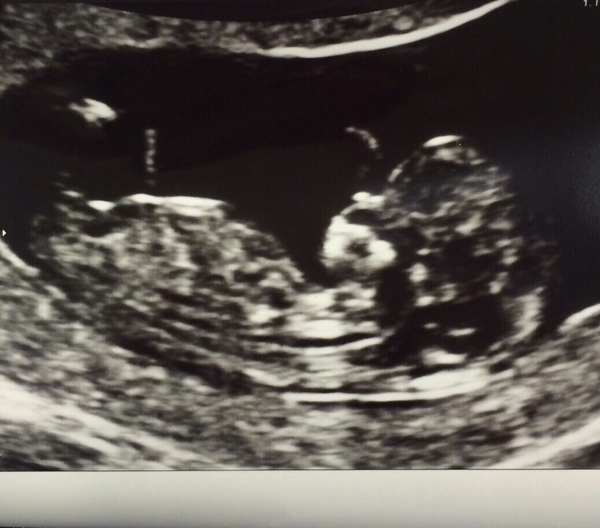

Just had my scan which was all rather surreal - bean opened and closed its mouth a few times which was cute and we got a wave! We were in there a while though as it wouldn't move from its back so the sonographer couldn't get all the measurements for ages!

lily lovely scan picture Smile

lily great scan picture Smile x

Lovely scan pic Lily!